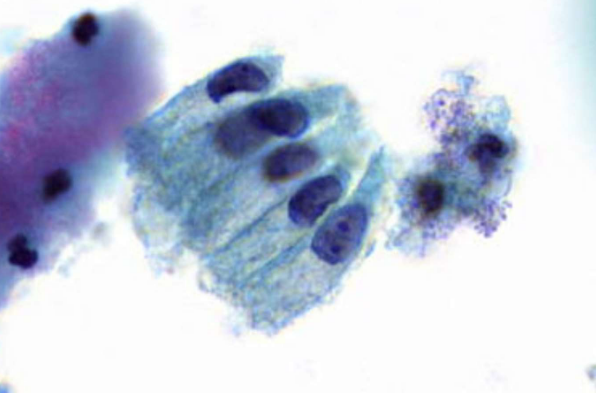

squamous metaplasia

squamous cell carcinoma